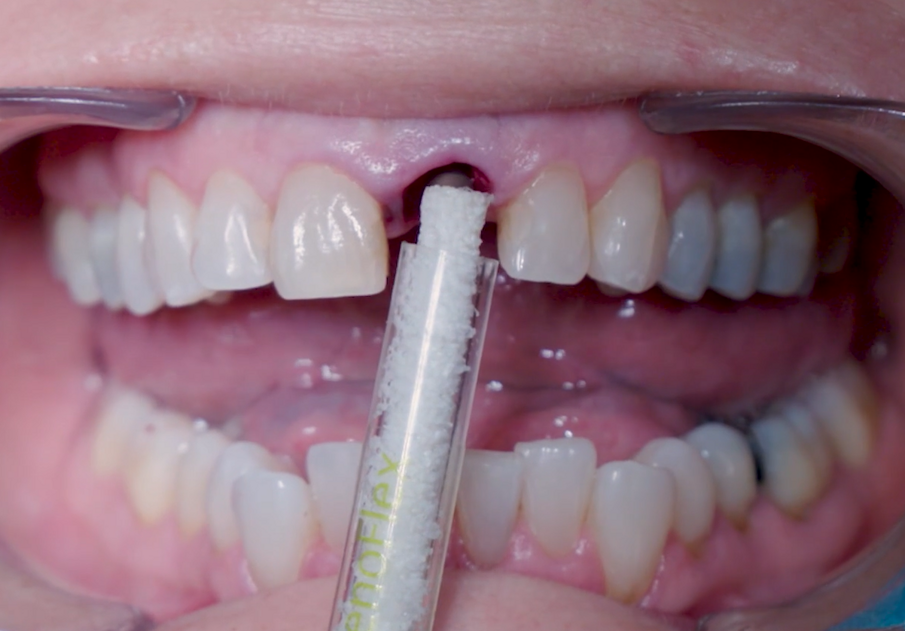

Dopo l’inserimento, la posizione dell’impianto è stata verificata orizzontalmente con uno specchio occlusale e verticalmente con una sonda chirurgica e a questo punto è stata selezionata l’altezza gengivale dell’abutment (Figg. 11, 12). Un abutment di guarigione è stato posizionato sull’impianto (Fig. 13) per proteggere la connessione in modo che l’osseo granulare sostitutivo (Straumann XenoFlex) potesse essere applicato nella fessura tra l’impianto e la parete vestibolare. Questo è stato delicatamente compattato con il lato di 2,8 mm della sonda chirurgica (Figg. 14–16). Il Collacone (biomateriali botiss) è stato utilizzato per tenere i granuli ossei lontano dai margini gengivali, allo scopo di evitare la fenestratura dei tessuti molli e l’infiltrazione fibroblastica (Figg. 17, 18).

Figg. 14, 15_XenoFlex Straumann applicato sulla cresta vestibolare.

Fig. 16_Condensazione dei granuli con sonda chirurgica.